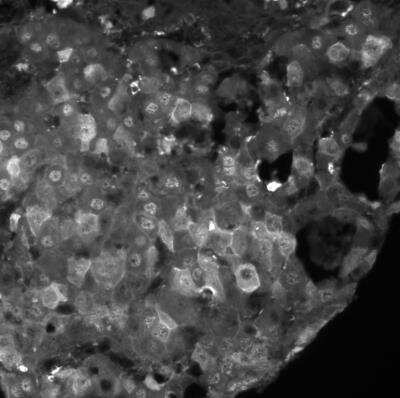

Immunohistochemistry: Arginase 1/ARG1/liver Arginase Antibody - BSA Free [NBP1-32731]

Arginase-1-ARG1-liver-Arginase-Antibody-Immunohistochemistry-NBP1-32731-img0033.jpg